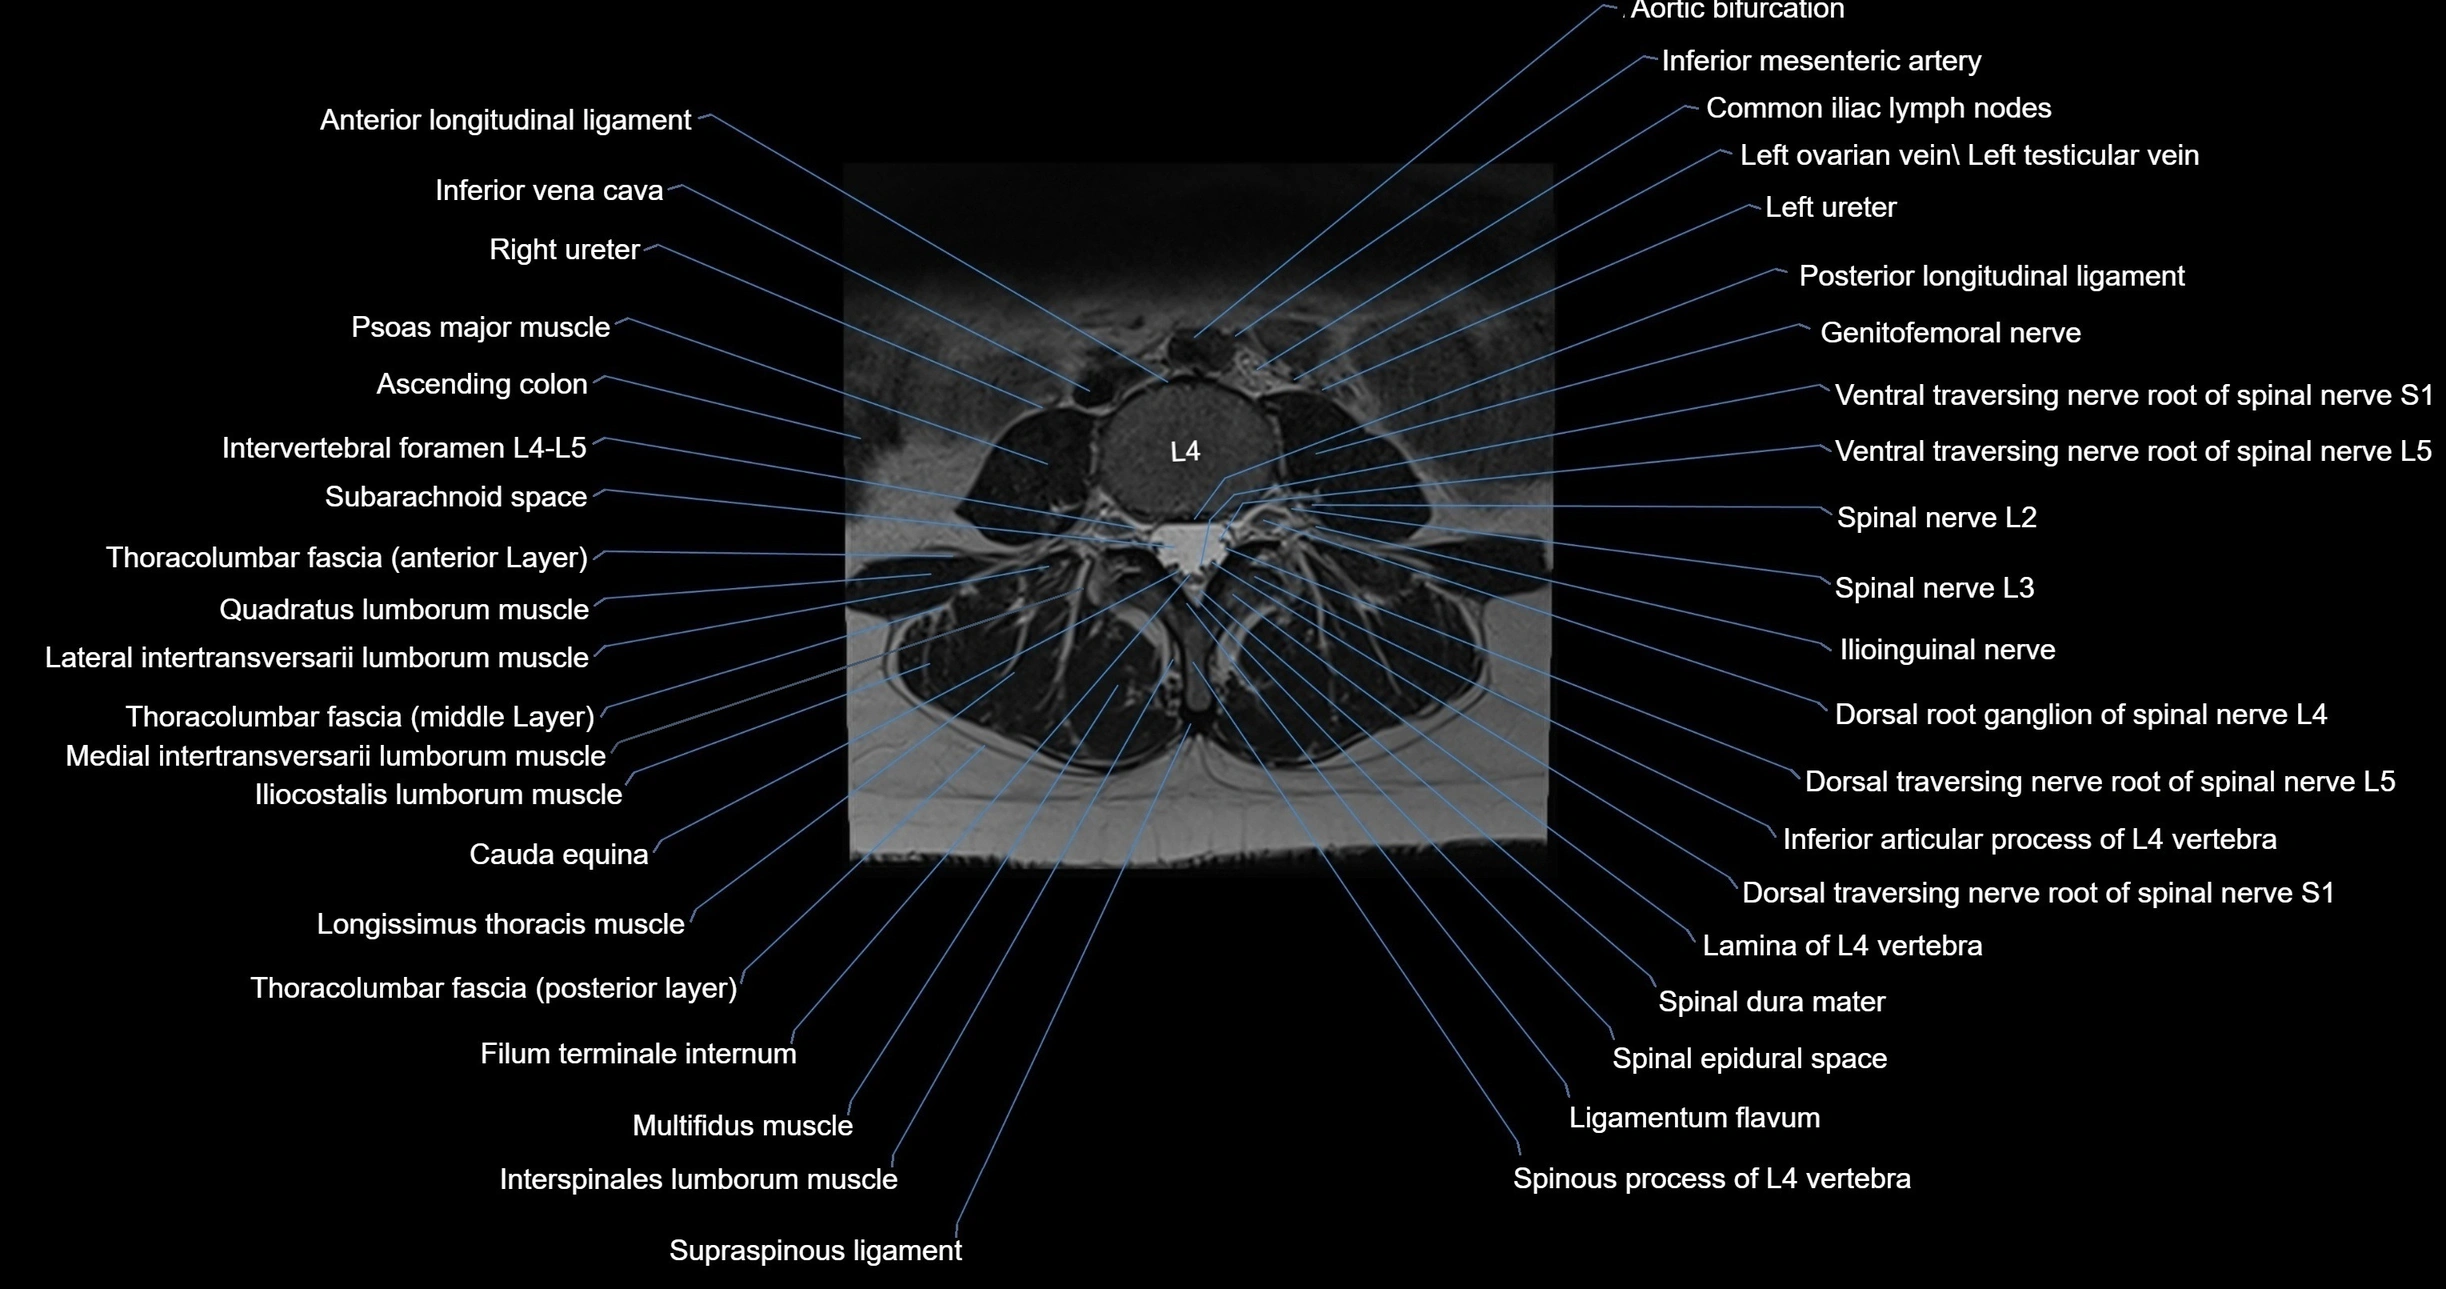

MRI images